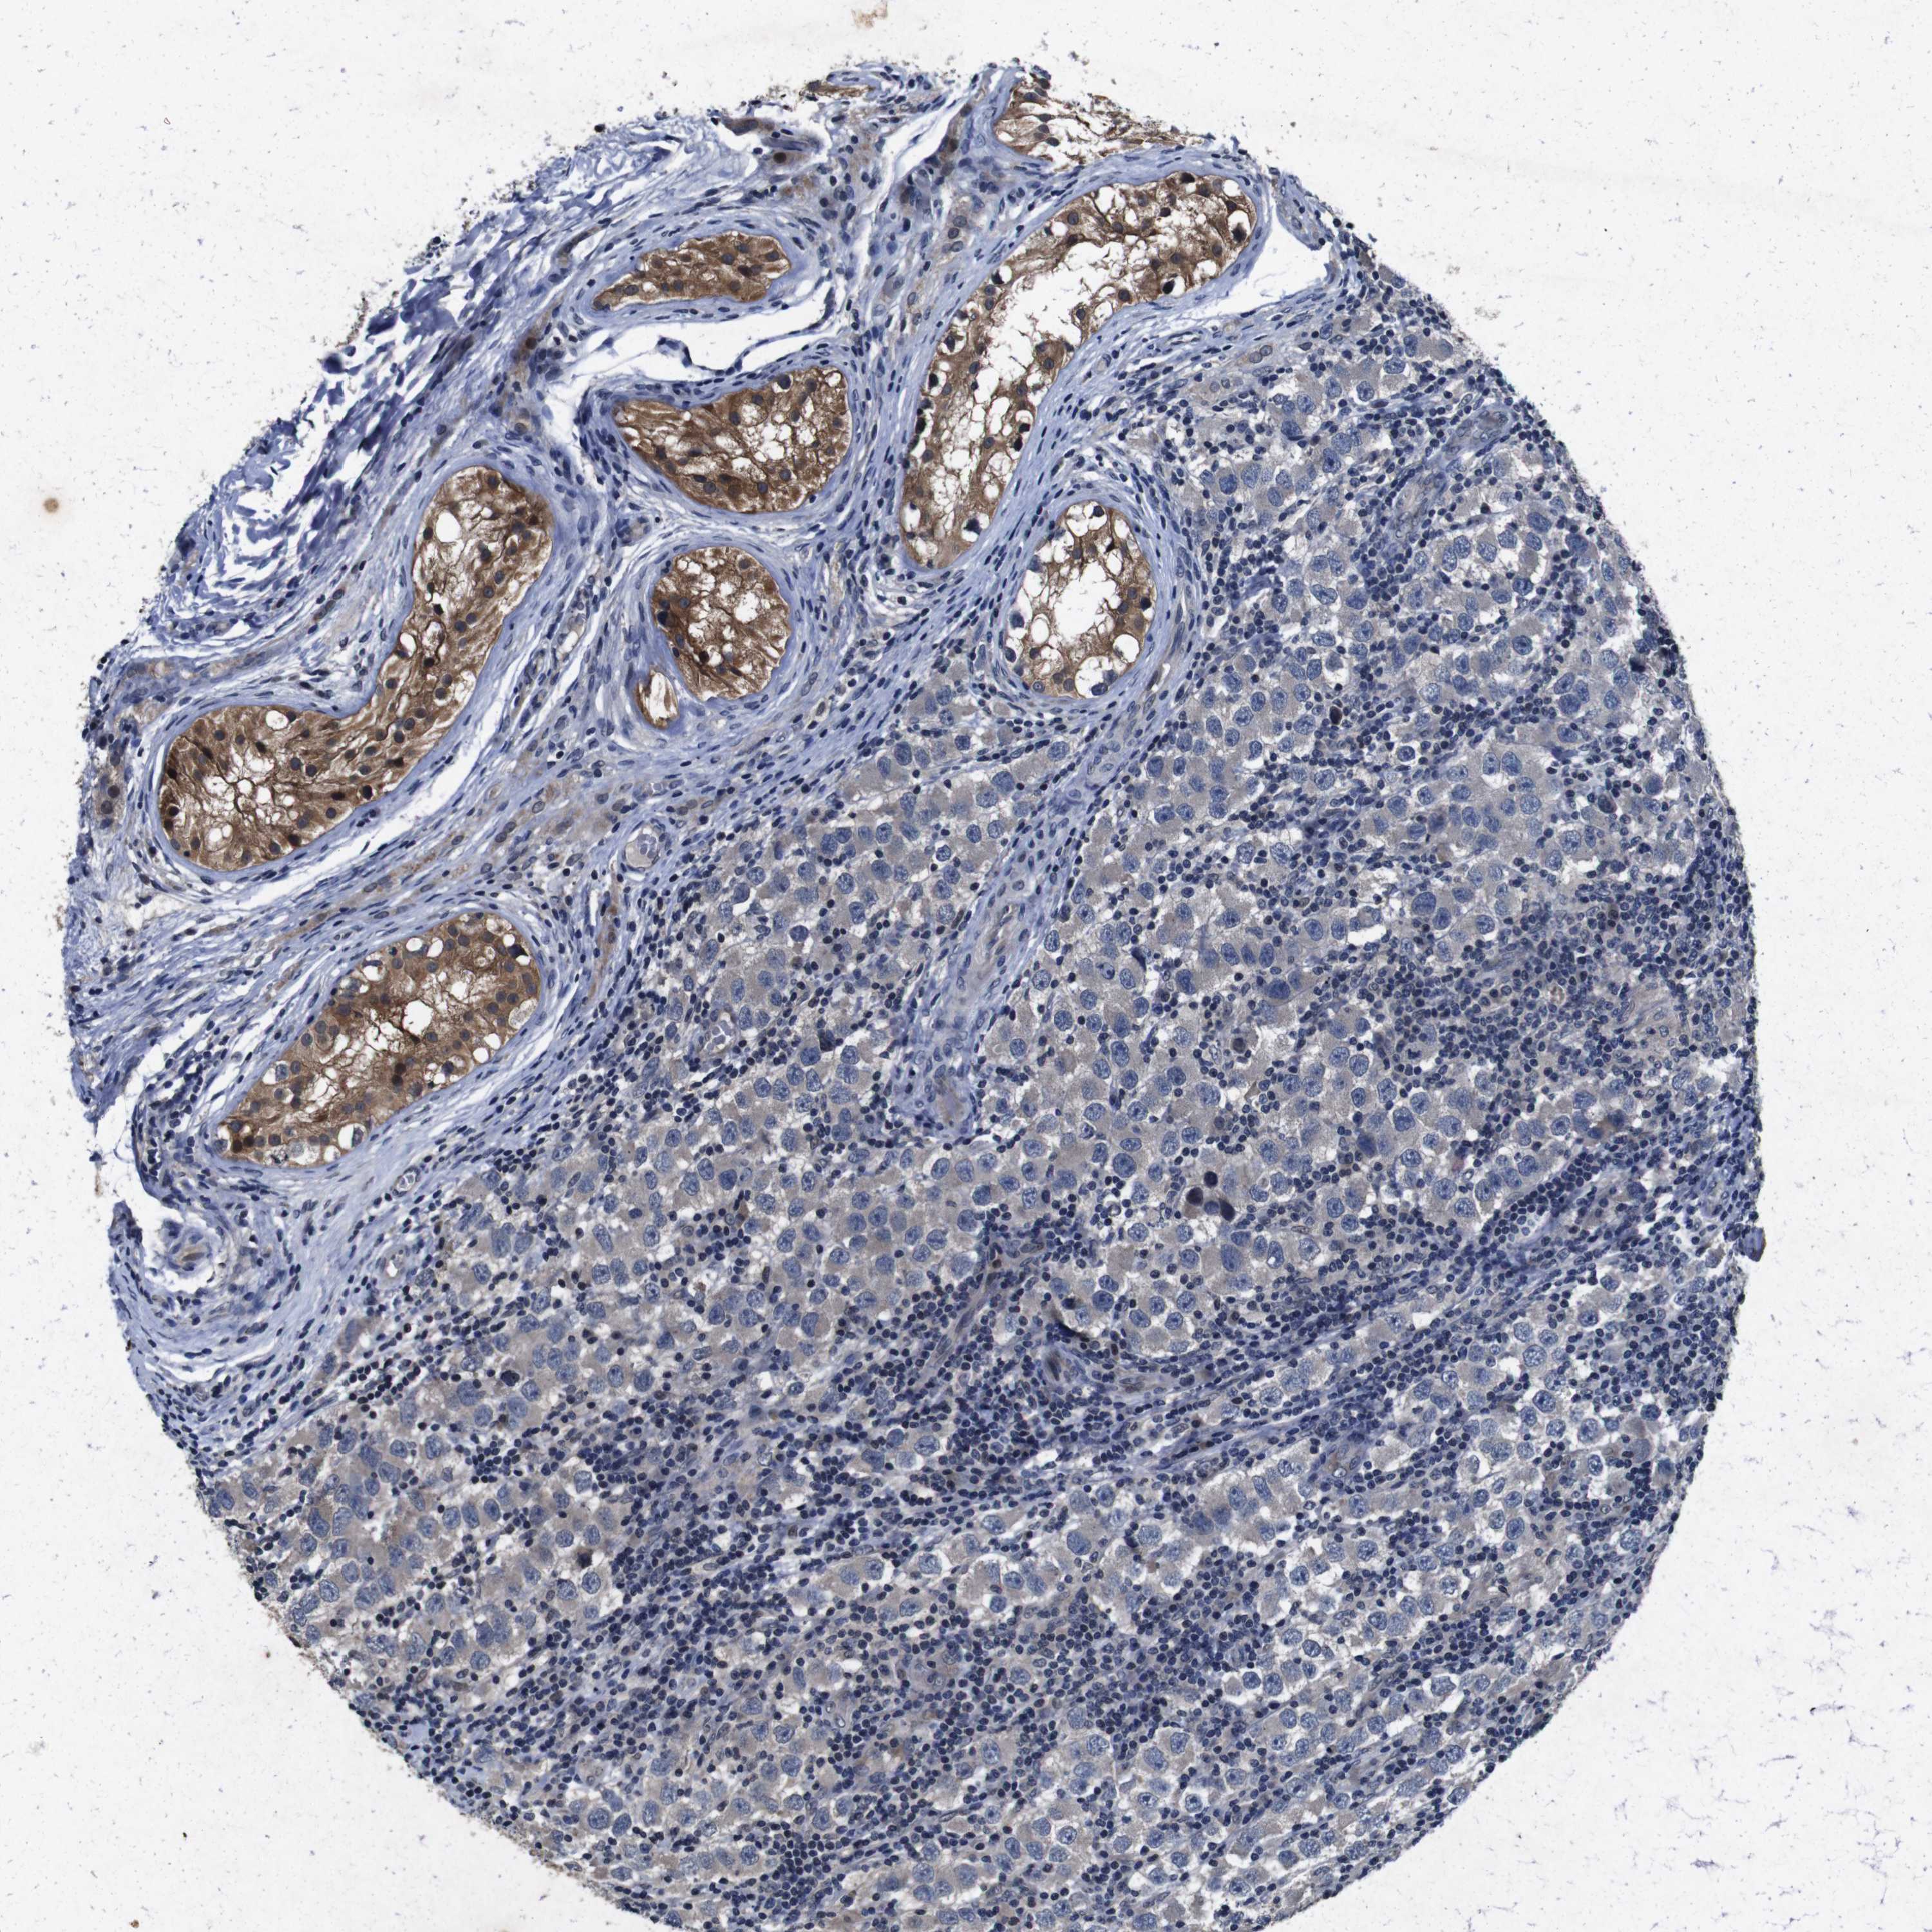

TESTIS CANCER - Protein expressioni

A mouse-over function shows sample information and annotation data. Click on an image to view it in a full screen mode. Samples can be filtered based on level of antibody staining by selecting one or several of the following categories: high, medium, low and not detected. The assay and annotation is described here.

Note that samples used for immunohistochemistry by the Human Protein Atlas do not correspond to samples in the TCGA dataset.

Antibody stainingi

Antibody staining in the annotated cell types in the current human tissue is reported as not detected, low, medium, or high, based on conventional immunohistochemistry profiling in selected tissues. This score is based on the combination of the staining intensity and fraction of stained cells.

Each image is clickable and will lead to virtual microscopy that enables deeper exploration of all samples and also displays staining intensity scores, fraction scores and subcellular localization as well as patient and tissue information for each sample.

Antibody HPA026441

Antibody CAB013090

Staining

High

Medium

Low

Not detected

Intensity

Strong

Moderate

Weak

Negative

Quantity

>75%

75%-25%

<25%

None

Location

Nuclear

Cytoplasmic/membranous

Cytoplasmic/membranous,nuclear

Carcinoma, Embryonal, NOS

Seminoma, NOS